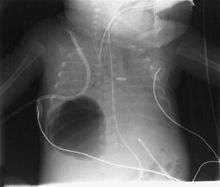

Diagnosis can be made using chest X-ray; the lesion shows up as a small, round area filled with air.[1] Computed tomography can give a more detailed understanding of the lesion.[1] Differential diagnoses, other conditions that could cause similar symptoms as pneumatocele, include lung cancer, tuberculosis, and a lung abscess[1] in the setting of Hyper IgE syndrome (aka Job's syndrome) or on its own, often caused by Staphylococcus aureus infection during cystic fibrosis.